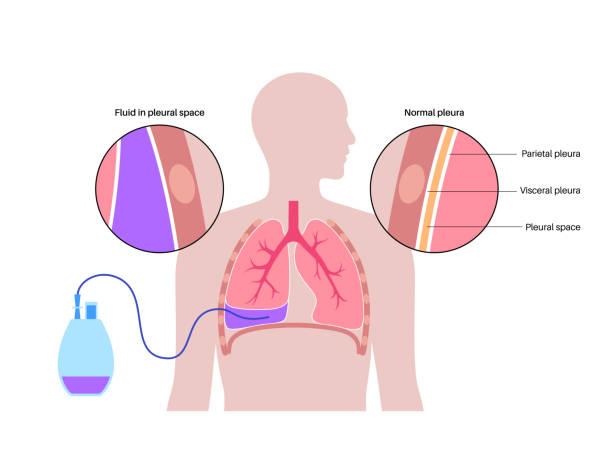

Le professeur Philippe ASTOUL, chef du service d'oncologie thoracique, maladies de la plèvre et pneumologie interventionnelle à l'hôpital Nord de Marseille, et co-auteur de ce travail, explique que les pleurésies malignes métastatiques sont fréquentes et nécessitent un traitement complexe, dans l’idéal adapté à chaque situation clinique (et notamment oncologique) qui n’empêche pas les récidives dans 50% des cas. Ces pleurésies malignes et leurs récidives sont corrélées à la survie des patients. Il précise que le liquide nécessite d’être évacué régulièrement pour des raisons de confort du patient mais également oncologiques et que, pour cela, il existe plusieurs méthodes, à adapter au cas par cas. Parmi ces méthodes, on trouve la pose d’un drain thoracique à demeure appelé encore cathéter pleural tunnelisé, qui peut être géré à domicile par des infirmières formées à la technique, selon différentes modalités d’évacuation du liquide pleural, quotidiennement ou en fonction des symptômes. Les inconvénients de cette technique sont liés à la présence d’un corps étranger, la douleur et le risque infectieux. Une autre technique consiste à réaliser une symphyse pleurale par talcage, à l’aide de talc calibré, dans l’idéal par thoracoscopie. L’inconvénient est une hospitalisation plus ou moins prolongée ce qui outre son désagrément pour le patient, augmente le coût de la prise en charge..

Philippe ASTOUL souligne que les résultats de ce travail ont montré que la combinaison du cathéter pleural tunnelisé et du talcage permettait de raccourcir la durée d’hospitalisation et la durée de drainage à domicile. Ceci est réalisé lors d’une thoracoscopie médicale, qui permet de plus d’explorer de façon rigoureuse la cavité pleurale, de réaliser des biopsies pleurales de bonne qualité. Le talcage est réalisé puis le drain est posé via le même orifice. Le patient ne reste alors que 24 heures en hospitalisation. Il insiste donc sur l’efficacité de ce geste combiné qui diminue le risque de récidive, permet une évaluation pleurale de bonne qualité, raccourcit la durée de drainage, diminue le risque infectieux et donc améliore le confort du patient. Philippe ASTOUL émet simplement la remarque que la perception d’un corps étranger thoracique est différente selon les pays, et qu’il serait judicieux d’évaluer cette question en fonction des approches culturelles par de nouvelles études.